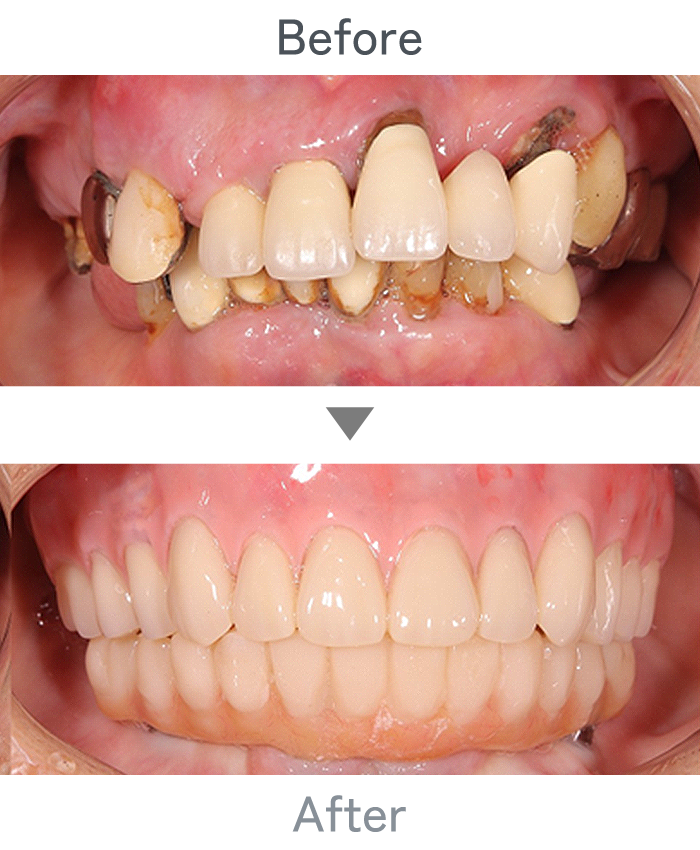

インプラント治療

+

ラミネートべニア

前歯のインプラント

主訴 前歯折れた

治療法 左上1番:インプラント治療

右上1番:ラミネートべニア

治療期間 4ヶ月半

費用 ・インプラント左上1番:300,000円

・インプラント左上1番上部構造:120,000円

・ラミネートべニア右上1番:100,000円

小 計:520,000円

消費税:52,000円

合 計:572,000円

※インプラント体、上部構造ともに『10年保証』

副作用

• メンテナンスが必要